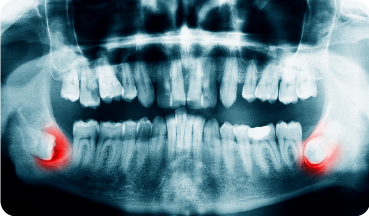

親知らずは、大臼歯(大人の奥歯)の中で最も後ろに位置する歯で、前歯から数えて8本目の歯のことをいいます。一般的には20歳前後に生えてくることが多く、個人差があり生えてこない人もいます。斜めに生えたり、歯ぐきに埋まったりするなど、歯並びに悪影響を及ぼしたり、炎症や痛みがでたりする場合には抜歯が必要です。